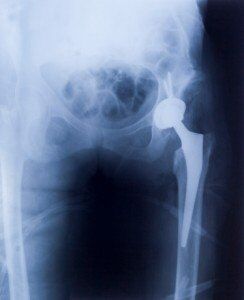

The Stryker Citation is a hip replacement component tipped with titanium. Used along with the Accolade and Meridian, the Citation constitutes parts of a hip implant. Approximately 20,000 people are using Stryker hip replacements in the United States alone. But the implants have been coming under fire for the same reasons many other metal-on-metal hip replacements are coming under fire: Premature failure and metallosis.

The problem with many Stryker hip replacements is that they are more difficult and traumatic to remove. The entire femoral system has to be removed in the case of failure, because the component is designed to promote a bony ingrowth, using porous coating. The implants are meant to become a permanent part of the body. The models that use this are the Stryker Rejuvenate and ABG II.